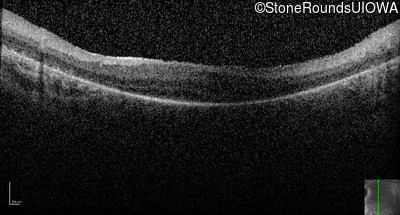

Optical Coherence Tomography - Right -

No Light Perception

Exemplar

Expanded OCT Stack

×